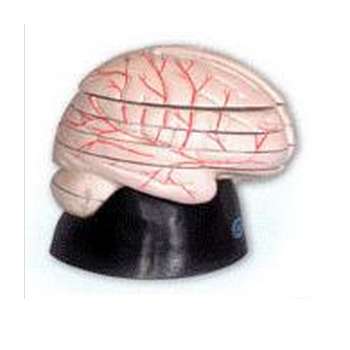

腦水平切面模型 GD/A18208產(chǎn)品概述:1、模型由大腦水平切面6個部件組成。顯示大腦水平切面解剖結構的形態(tài)位置及其毗鄰關系。大腦水平切面可顯示大腦內(nèi)部結構, 包括基底核的組成(豆狀核和尾狀核)、內(nèi)...